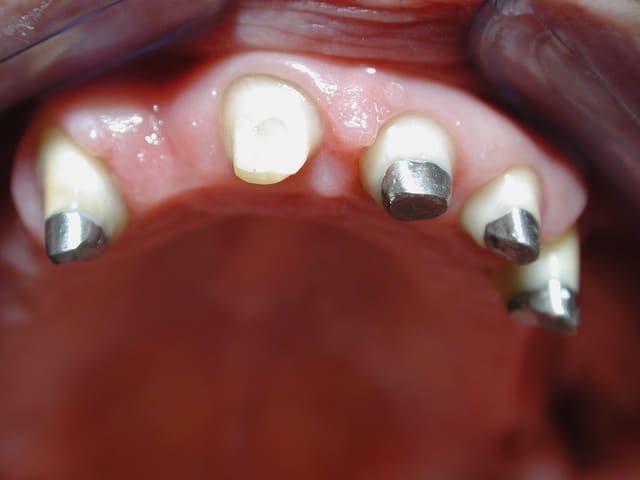

Voila un cas vite fait par un rentable: ramolli en 5 ans

Tu penses qu'on peut le rattraper en faisant inlay-core + bridge ?

Tu penses que j'ai perdu mon temps pour justifier des séances ?